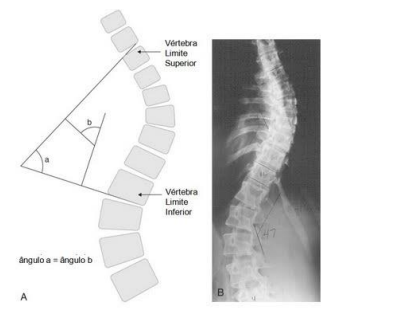

O ângulo Cobb é a medida mais utilizada para diagnosticar escoliose e, consequentemente, acompanhar

o progresso da deformidade da coluna vertebral. A imagem seguinte demonstra que existe: